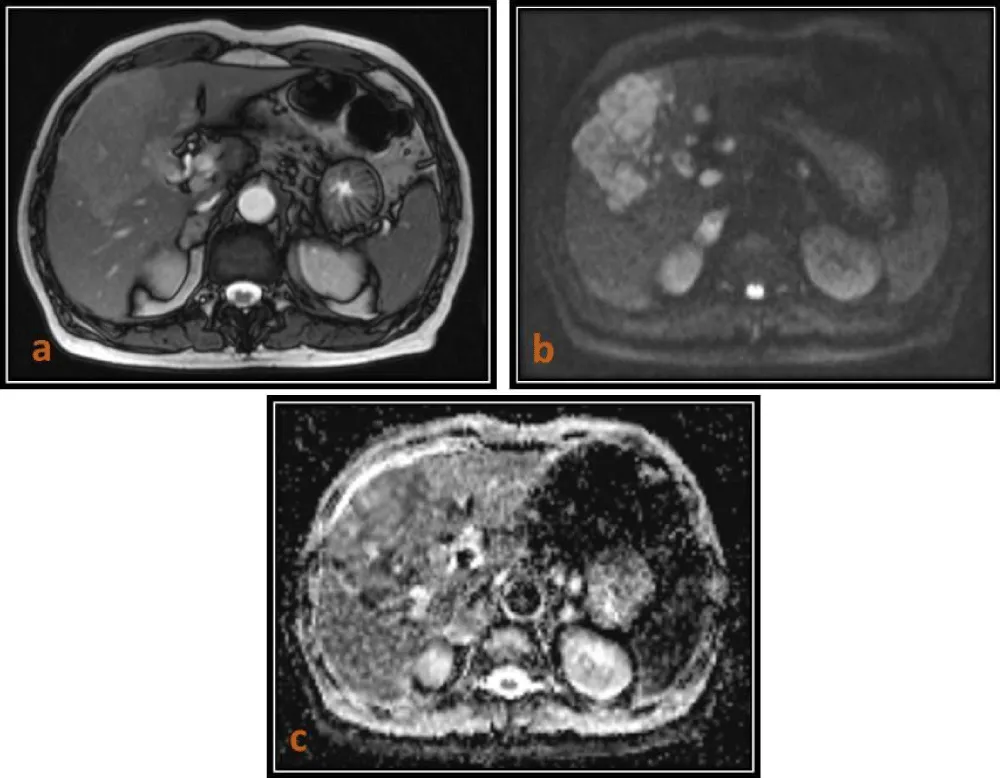

In our study, hepatic cysts demonstrated the highest ADC values, followed by hemangiomas, whereas malignant lesions such as HCC and metastases showed significantly lower ADC values. The mean ADC values of malignant lesions were significantly lower (0.90 ± 0.15 × 10-3 mm2/s) (Figures 1,2,4) than those of benign lesions (2.19 ± 0.29 × 10-3 mm2/s) (Figure 3), and this difference was statistically significant, in agreement with previous studies [10]. However, no significant difference was observed between primary (0.89 ± 0.15 × 10-3 mm2/s) and metastatic malignant lesions (0.90 ± 0.14 × 10-3 mm2/s), which may be attributed to the relatively small sample size.

Download Image

Figure 1: 54 year-oldmale patient with HCC. (a) Axial T2(TruFISP)-weighted image shows a hyperintense lesion in segment IVa of the liver, which is markedly hyperintense on DWI (b = 800) as seen in image (b) and hypointense on ADC map as seen in image (c) with a low ADC value (0.912 x 10 mm2/s).